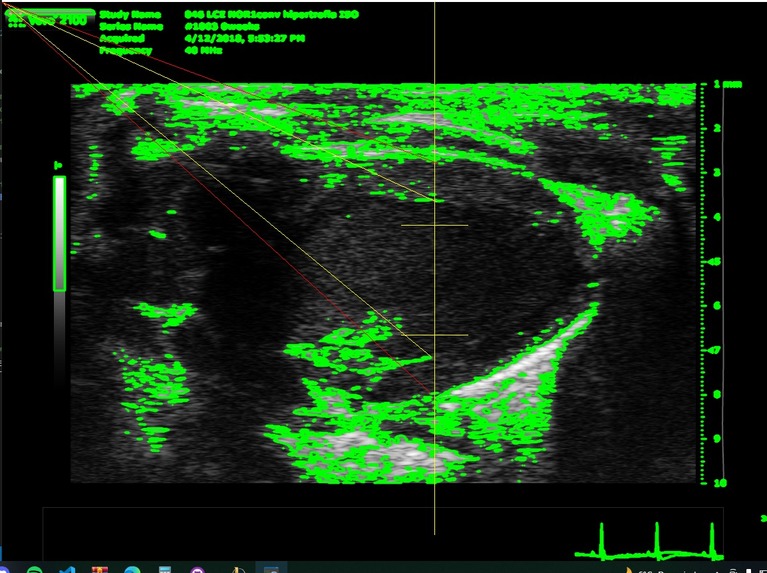

Its a CLI's program where have to give a psla and sax dicom files path. Then gets some variables from the files to throw some conclusions (if it's a healthy heart or not) and also it save it as excel file.

We built it as a python project with its virtual environment with the requirements needed, also needs a special program called Theseract that it is a optical character recognition open source to get the BPM from the files, the rest of the needed parameters are calculed using opencv mainly.

The most significative challenge that the team ran into consisted in the identification of the contourns of the image. Differenciating between the underside and the outer layer of the blood vessel ended up being an arduous task

What's next for DICOM analysis heart hypertrophy

Alongside the existing metrics that might indicate the existence of hypertophy, the usage of both supervised and unsupervised machine learning methods could be considered so as to improve the precision of the obtained results, improve the sistole and diastole detection and add new functionalities as read directories and custom save.